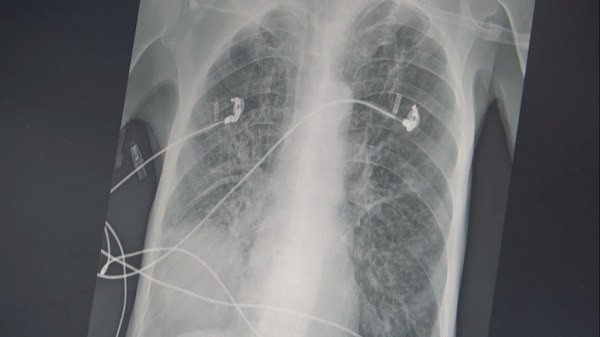

SİGARA NASIL KOAH YAPAR?

Akciğer keseciklerinin tıpkı bir balon gibi olduğunu ifade eden Prof. Dr. Özkaya, "Temiz havayı nefes olarak bu keseciklere aldığınızda şişer ve hava ile dolunca elastik yapısından dolayı içerdeki kirli havayı da tıpkı balonun sönmesi gibi dışarı atar. Ancak sigara içerseniz, kesecik duvarlarınızdaki elastik doku harap olur ve esneme yeteneğini kaybederek tıpkı bu naylon poşet gibi olur. Nefes alırsınız ama balonun elastik yapısı olmadığı için kirli havayı dışarı atamazsınız ve içerde kirli hava kalır. Siz yeni bir temiz havayı nefesle almak istediğinizde keseciklerde temiz havanın gireceği yer kalmayacak ve nefes alamama yani nefes darlığı başlayacak" şeklinde konuştu.